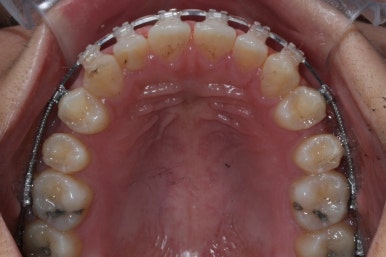

장치 부착 모습입니다.

이번에 부산치아교정치과에서 사용한 장치는 클리피씨라는 자가결찰 세라믹입니다.

장점으로는 다음과 같습니다.

세라믹이라 눈에 잘 띄지 않습니다.

철사를 잡아주는 캡이 장치에 달려 있어서 사용도 간편하고 치료시간도 짧아집니다.

금속,세라믹, 투명교정장치 든 각각 장단점이 있기 때문에 교정전문의와의 상의 후에 기호에 맞게 선택하시면 되겠습니다.